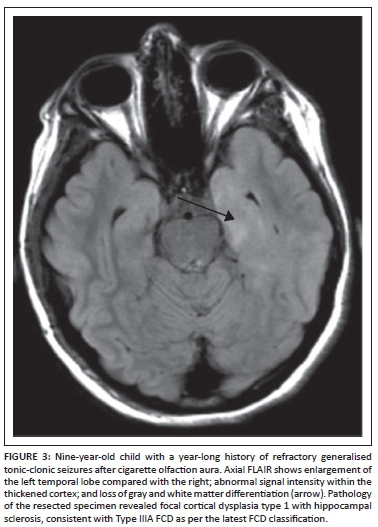

Tuberous sclerosis complex (TSC) is a multisystem genetic disorder of variable phenotypic expression, with an incidence of about 1 in 5800 live births worldwide.19 The disorder results from a mutation in the TSC1 gene in chromosomal region 9q34 or the TSC2 gene in chromosomal region 16p13, and is inherited in an autosomal dominant fashion. Up to two-thirds of cases result from spontaneous genetic mutation. Clinical manifestations of tuberous sclerosis include seizures, autism, developmental delay, and behavioural and psychiatric disorders. Epilepsy is common in patients with TSC, occurring in up to 90% of affected individuals during their lifetime.19 Up to one-third of children will develop infantile spasms. Although not completely understood, the incidence of epilepsy is thought to relate to the neuropathologic features of the disorder, including cortical tubers and other dysgenetic features. Individuals with TSC frequently have epileptiform features on their electroencephalograms. In addition to medical therapies, surgery plays an important role in the management of children with drug-resistant epilepsy in TSC. The focus of pre-surgical evaluation in these patients is to identify the most epileptogenic tubers by multimodality non-invasive tests, including using a combination of MRI (Figure 6), PET (including [(11) C] methyl-l-tryptophan-positron emission tomography [AMT-PET]), ictal and interictal SPECT, and MEG. Based on this evaluation, a subset of patients with TSC can become suitable candidates for surgical resection. In some cases, subdural electrode placement may be required to identify a single or conglomerate of epileptogenic tubers.